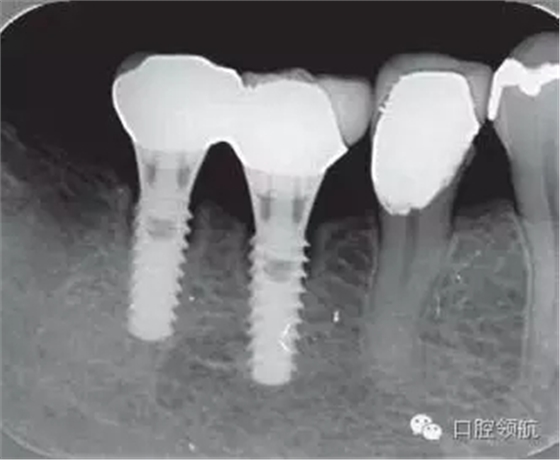

修復體安裝后的2003年1月復診時的X線片上,沒有發(fā)現(xiàn)種植體頸部有骨吸收現(xiàn)象,情況良好(圖2)。但是,2003年8月,因混合陶瓷樹脂部分修復體的破損而進行再制作時,發(fā)現(xiàn)有輕度的咬合疼痛以及舌側頸部的牙齦有輕壓痛。口內沒有觀察到該部位的牙齦紅腫。X線片可以觀察到(左下第6顆牙) 的種植體頸部有達到第4螺紋的骨吸收現(xiàn)象(圖3)。

圖3(左下第6顆牙)的種植體的骨吸收達到第4螺紋(2003年8月)